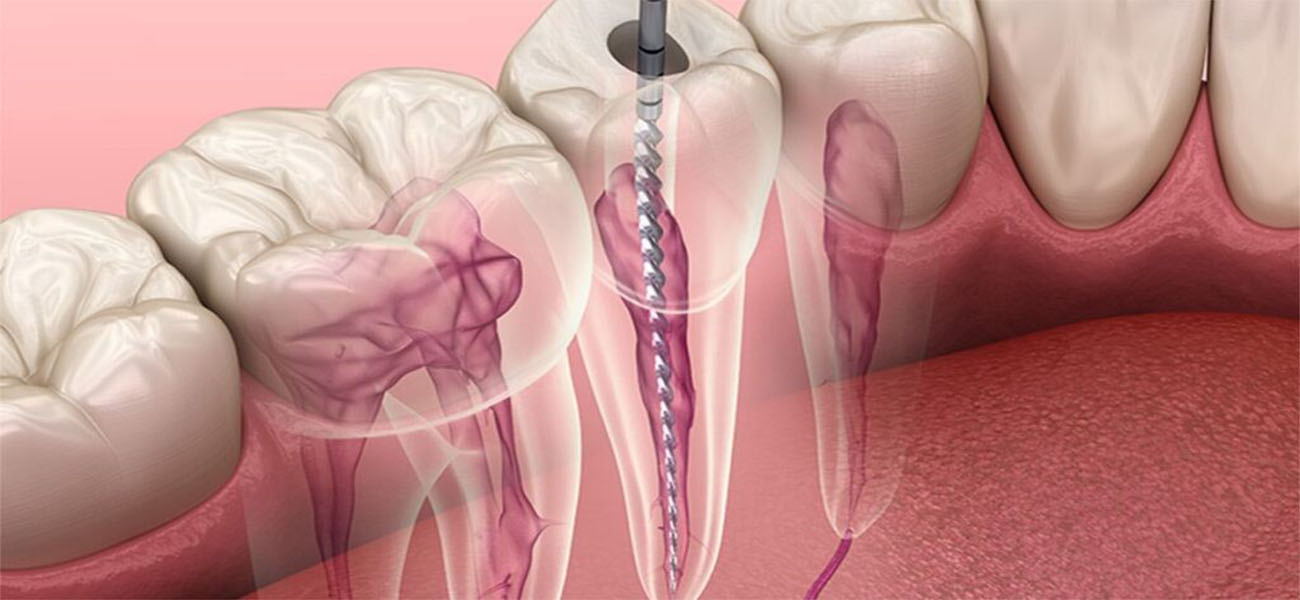

عصبکشی یا درمان ریشه، به منظور درمان عفونتها و آسیبهای دندانی انجام میشود. این فرآیند شامل حذف بافت عفونی از کانال ریشه دندان و پر کردن آن با مواد مخصوص است. عدم انجام این درمان میتواند منجر به درد شدید، عفونت و حتی از دست رفتن دندان شود.

کلینیک دکتر گیاهپور مجهز به جدیدترین تکنولوژیها و دستگاههای دندانپزشکی است. این تجهیزات شامل سیستمهای تصویربرداری دیجیتال، لیزرهای دندانی و ابزارهای پیشرفته برای عصبکشی است که به کاهش درد و افزایش دقت درمان کمک میکند.

عصبکشی یا درمان ریشه، یک فرآیند دندانپزشکی است که به منظور حذف بافت عفونی و آسیبدیده از کانال ریشه دندان انجام میشود. این درمان به حفظ دندانهای آسیبدیده و جلوگیری از عفونتهای بیشتر کمک میکند.

با استفاده از تکنیکهای مدرن و بیحسی موضعی، عصبکشی معمولاً بدون درد انجام میشود. بسیاری از بیماران پس از درمان احساس راحتی میکنند و درد کمی را تجربه میکنند.